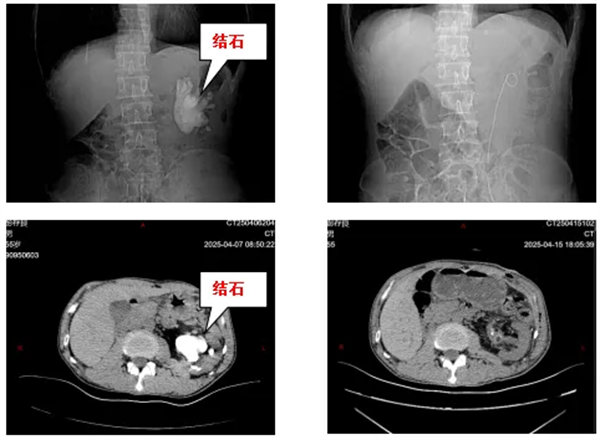

近日,寶雞市人民醫院泌尿外一科接診了一位特殊患者。張先生(化名)因持續腰痛就醫,檢查結果令人震驚:該患者只有一個腎,且唯一的左腎內竟藏有一個直徑達8cm的巨型鑄型結石,形如“鹿角”般盤踞整個腎盂系統,且質地異常堅硬,與腎盂黏膜緊密粘連。對于獨腎患者而言,這不僅關乎疼痛,更是一場生死考驗!

經過3小時的精細操作,醫療團隊成功完整取出所有結石分支。術后檢查顯示患者腎盂系統通暢,腎功能指標穩定?;颊咝g后恢復順利,術后一周即康復出院。